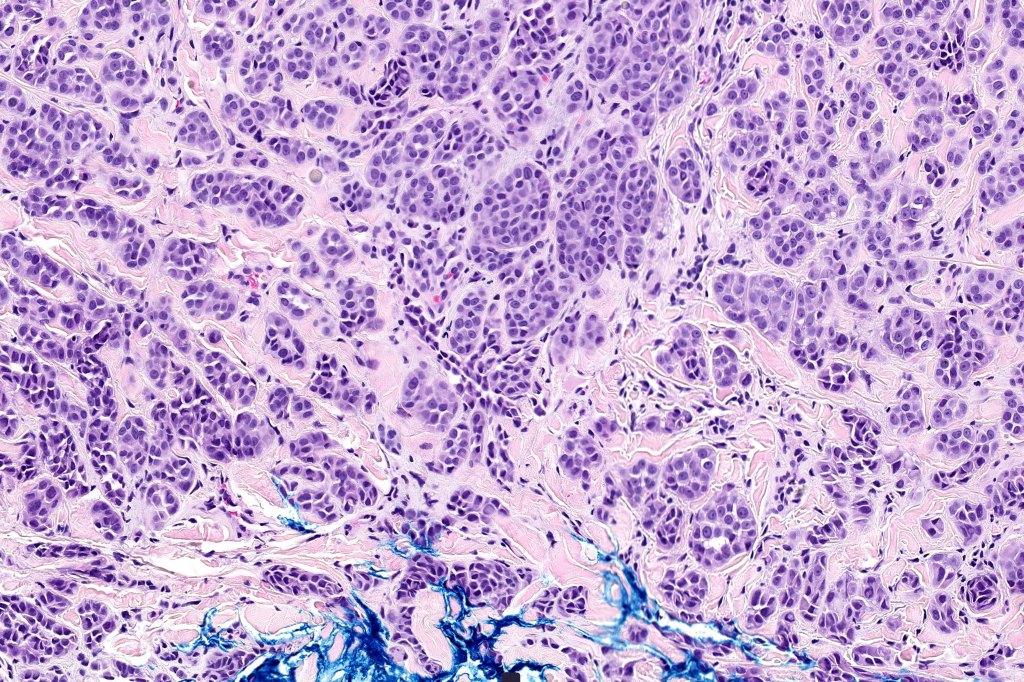

•Involve deep dermis or subcutis

•Large nodules which often show impaired maturation

•Loss of gradient with HMB45 and Ki67

•>20% Ki67 expression